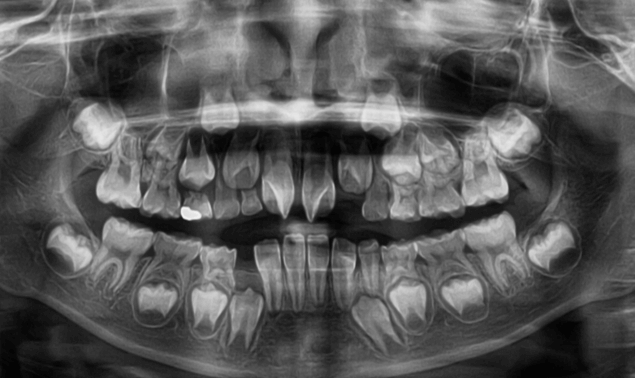

早期矯正治療 埋伏歯症例①

主訴 | 上顎の永久歯の位置がおかしいとのことで来院。萌出していない右上の前歯の状態に不安を抱えられていました。 |

---|---|

診断結果 | 8歳11か月の男児。早期対応が必要と判断されました。 |

治療内容 | 埋伏してる上顎右側をけん引するために、上顎にリンガルアーチを装着しました。 口腔外科医に開窓術を施術していただき、埋伏歯の牽引を開始しました。 |

治療後の経過 | 早期矯正治療終了後、3~4か月おきに定期検診を行います。 上下顎第2大臼歯(真中から7番目の永久歯)が生え揃い、上下顎骨の成長発育が落ち着いてから本格矯正治療を行います。 |

治療期間 | 動的治療期間:約3年2か月 |

治療費用 | 440,000円(税別) |